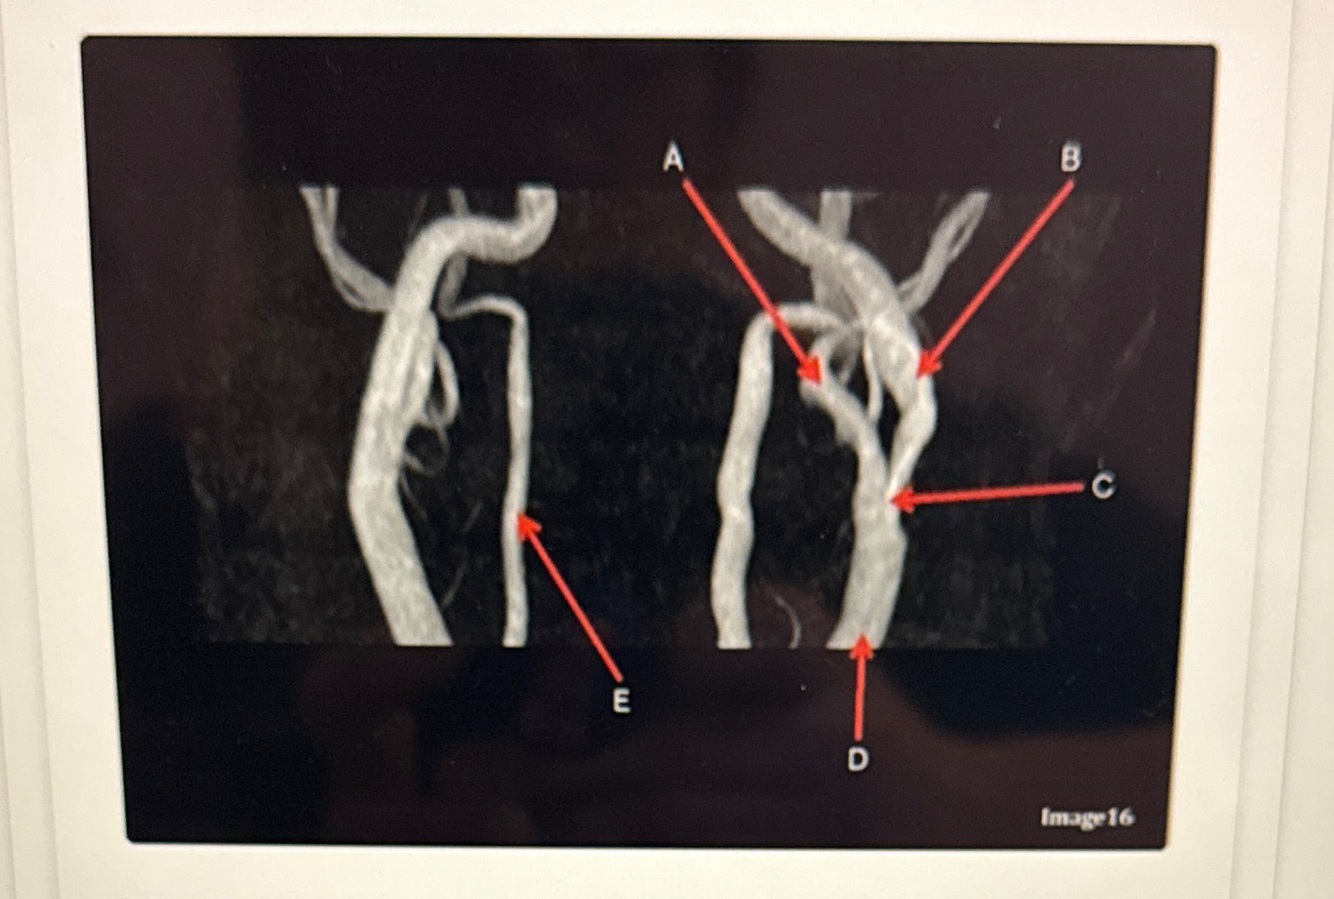

Letter A points to the

VertebroBasilar junction

Letter B points to the _______ and letter D points to the ______

B. External carotid artery

D. Vertebral artery